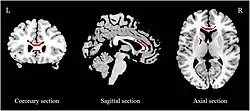

Structural neuroimaging

Meta analyses performed using seed-based d mapping have reported grey matter reductions in a number of frontal regions. One meta analysis of early onset general depression reported grey matter reductions in the bilateral anterior cingulate cortex (ACC) and dorsomedial prefrontal cortex (dmPFC).[101] One meta analysis on first episode depression observed distinct patterns of grey matter reductions in medication free, and combined populations; medication free depression was associated with reductions in the right dorsolateral prefrontal cortex, right amygdala, and right inferior temporal gyrus; analysis on a combination of medication free and medicated depression found reductions in the left insula, right supplementary motor area, and right middle temporal gyrus.[102] Another review distinguishing medicated and medication free populations, albeit not restricted to people with their first episode of MDD, found reductions in the combined population in the bilateral superior, right middle, and left inferior frontal gyrus, along with the bilateral parahippocampus. Increases in thalamic and ACC grey matter was reported in the medication free and medicated populations respectively.[103] A meta analysis performed using "activation likelihood estimate" reported reductions in the paracingulate cortex, dACC and amygdala.[104] Using statistical parametric mapping, one meta analysis replicated previous findings of reduced grey matter in the ACC, medial prefrontal cortex, inferior frontal gyrus, hippocampus and thalamus; however reductions in the OFC and ventromedial prefrontal cortex grey matter were also reported.[105][106] Two studies on depression from the ENIGMA consortium have been published, one on cortical thickness, and the other on subcortical volume. Reduced cortical thickness was reported in the bilateral OFC, ACC, insula, middle temporal gyri, fusiform gyri, and posterior cingulate cortices, while surface area deficits were found in medial occipital, inferior parietal, orbitofrontal and precentral regions.[107] Subcortical abnormalities, including reductions in hippocampus and amygdala volumes, which were especially pronounced in early onset depression.[108] Multiple meta analysis have been performed on studies assessing white matter integrity using fractional anisotropy (FA). Reduced FA has been reported in the corpus callosum (CC) in both first episode medication naive,[109][110] and general major depressive populations.[100][111] The extent of CC reductions differs from study to study. People with MDD who have not taken antidepressants before have been reported to have reductions only in the body of the CC[109] and only in the genu of the CC.[110] On the other hand, general MDD samples have been reported to have reductions in the body of the CC,[110] the body and genu of the CC,[100] and only the genu of the CC.[111] Reductions of FA have also been reported in the anterior limb of the internal capsule (ALIC)[109][100] and superior longitudinal fasciculus.[109][110]